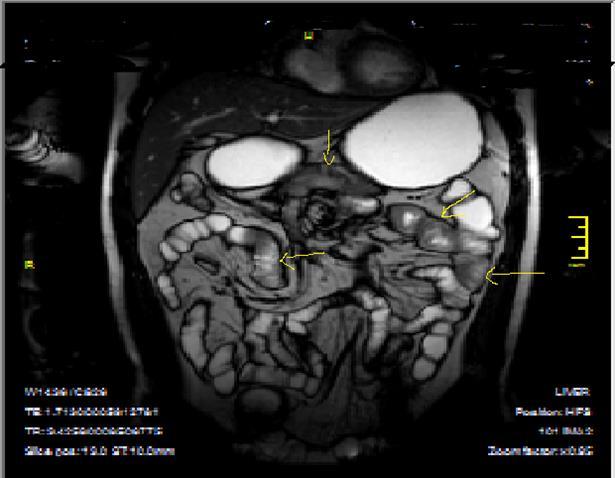

Pathognomonic signs of Crohn’s disease are; Bowel wall thickness must be higher than 2 mm in small intestine, 3 mm in colon, valvula conniventes has to be less than 3 mm, and small intestine diameter will be less than 3 cm, long segment intestinal infiltration, creeping fat sign, loss of haustration in colonic segments, skip lesions between normal and diseased segments and transmural invasion of bowel wall2, 5, 12, 14,18, 19, 20. In endoscopy; Aftos ulcerations and erosions are found out initially in the normal bowel mucosa than at later stages, mural stratification with longitudinal and transverse ulcerations are observed7, 14, 20, 21. On MRI; High bowel wall enhancement is particular at active inflammation, increased signal at bowel wall and adjacent mesentery on T2W images, strictures-fistulization and abcesses are the main complications and hyperintense on T2W images, asymmetrically thickened mucosal folds and lymphadenopathy, mesenteric stranding of the effected bowel wall and prominent draining vessels of the inflamed intestinal loops(comb sign), presence of intramural fat at chronic phase and target sign due to wall thickening at acute phase, surrounding peri-intestinal edema in acute phase are the main findings of Crohn’s disease7, 12, 14,18, 19, 20, 21 (Figure 2a-b)

Bowel wall thickening with increased luminal and extra-luminal signal changes on FS images, showing active inflammation, edema in the adjacent intraperitoneal and mesenteric spaces, active inflammation; bowel wall thickening and enhancement on post-contrast T1W images plus high signal intensity on T2W- FS images7, 9, 12, 14, 17, 18, 19, 20, 21 (Figure 4a-b).

Chronic disease without active inflammation; Bowel wall thickening and enhancement on postgadolinium T1W images plus low signal intensity on T2W-FS images with possible stenosis and obstruction due to fibrosis, chronic disease with active inflammatoryexacerbations;these conditions can overlap with active inflammation, require longitudinal repeated scanning7, 12, 14, 20,26, 27, 28, 29, 30 (Figure 5a-b, Figure 6a-b)

Figure 4a.Mucosal involvement and lack of opacified ileal segments with loss of intestinal folds and increased bowel wall thickness due to Crohn’s disease on T2W coronal sequence after OCA, presented at 37 years old male with moderate Crohn’s disease.

Figure 4b.Mucosal, luminal and bowel wall involvement in Crohn’s disease with skipped lesions, seen at T2W axial image after OCA, presented at 45 years old male with severe inflammatory disease.